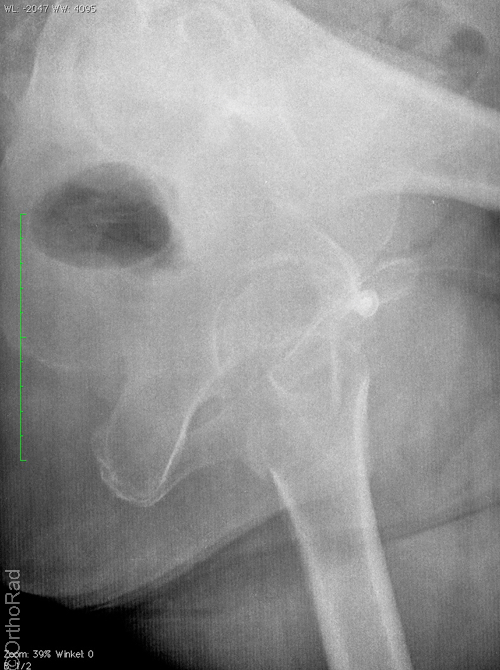

HüftTEP Luxation